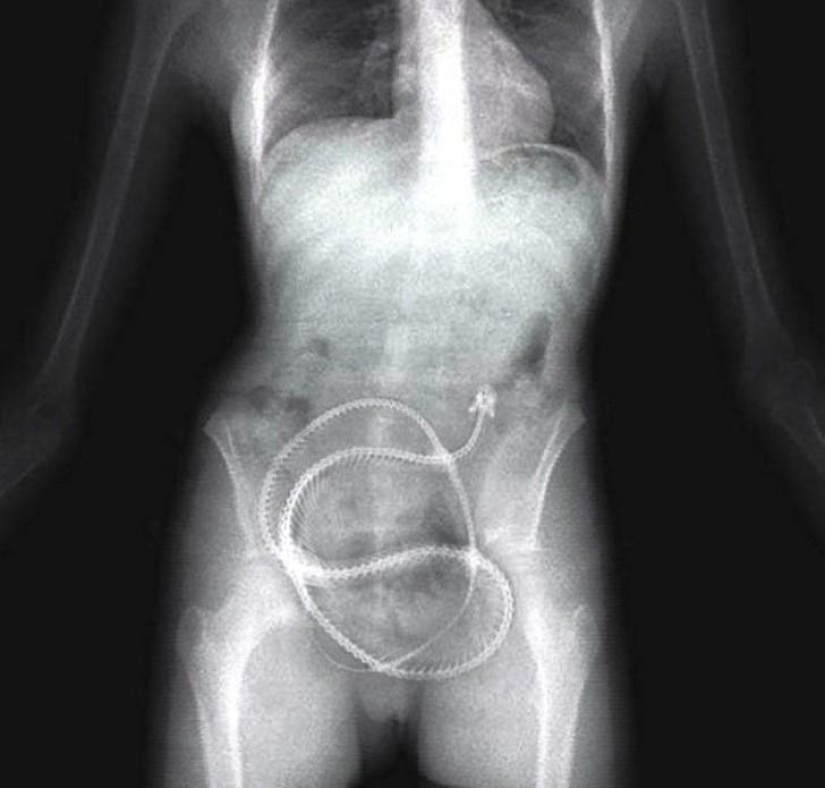

Bed springs.